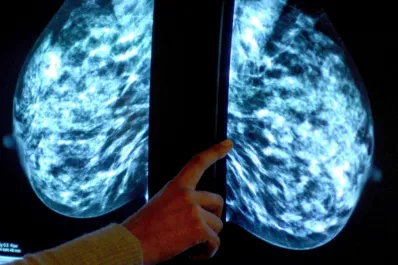

Cáncer de mama: a qué signos debemos estar atentos en un autoexamen

Una especialista describe cuáles son los síntomas que podemos observar o palpar en las mamas y que podrían ser indicios de cáncer

Cinco datos que tenés que saber sobre el cáncer de mama

Durante todo octubre autoridades sanitarias llevarán adelante una campaña de concientización sobre la importancia de la prevención y detección temprana.